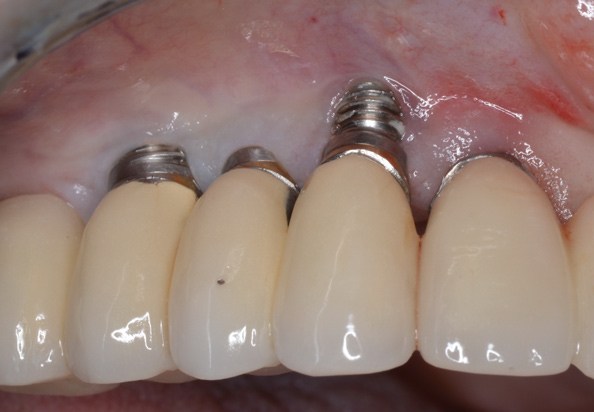

(13.) Reverse torqueing allows for a nonsurgical implant removal. No bone was sacrificed in removing these three implants.

Figure 13

(14.) One-time use reverse torque components were used to remove these implants. Portions of osseointegrated bone are still attached in the apical region.

Figure 14

In the reverse torque method, high torque values of up to 200 Ncm are applied to the internal aspect of the implant to overcome the strength of the bone-to-implant contact (ie, osseointegration) and "fracture" the implant from it's osseous housing. The implants can then be easily rotated counterclockwise out of the site (Figure 13 and Figure 14). It is important to note that the strength of osseointegration may be significant and above the threshold of reverse torque devices. This can lead to fracture of the implant or the instruments used. If this occurs, it is usually necessary to utilize a trephine to complete the implant removal. For cases in which potential fracture during reverse torque instrumentation is anticipated, such as those involving wide, long, or hollow implants, many of the reverse torque kits contain thin trephine drills. These are intended to be used in the coronal aspect to separate the cortical bone at the crest, reducing the force necessary to reverse torque implants out of their osteotomies. Because these trephines are ultrathin, they are prone to fracture and are not meant to be used along the entire length of the fixture being removed. In addition, it is critical to only use these trephines in a vertical direction. Attempting to luxate an implant while it is inside the trephine will likely fracture the trephine. If this occurs, wider trephines or piezoelectric bone saws will be necessary to remove the retained portion of the fractured trephine. When reverse torque kits are used cautiously, bone can be preserved and immediate implant replacement can be considered.